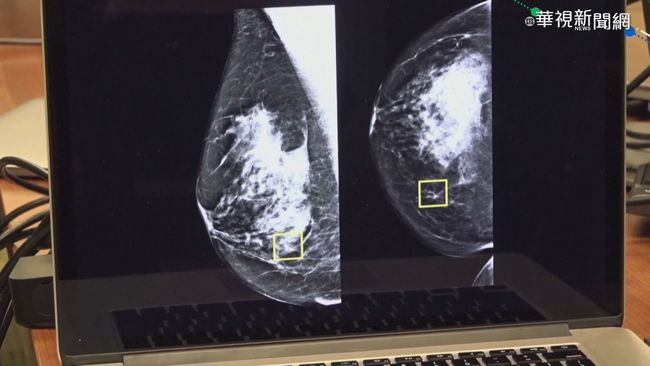

圖片來源:華視